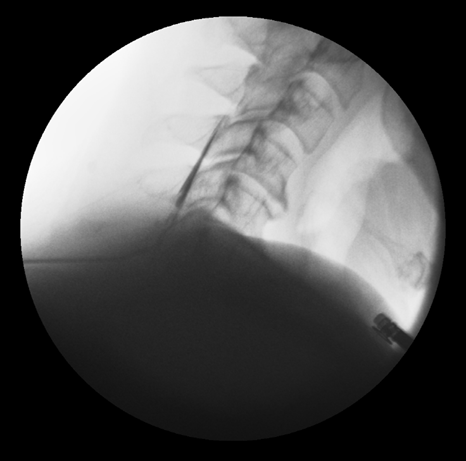

그림12.png 촬영 일시: 2025.04.19

<Fig 3. 특수 카테터로 병변에 직접 약물을 주입하여 신경염증을 제거하는 영상>

약 1시간 정도의 시술을 마치고

회복실에서 휴식을 취하시는 동안

환자분께서 목을 조심스럽게 좌우로 돌려보시더니

"어? 아까보다 훨씬 부드러워졌는데요?"